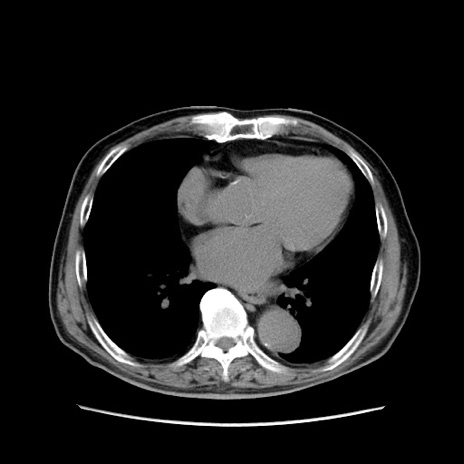

症例24(横断像)

【症例】80歳代男性

【主訴】左側腹部痛、嘔吐

【現病歴】本日早朝より左腹部に痛みあり。昼頃嘔吐認めたため、救急要請。

【既往歴】直腸癌(Mile手術)、胆摘

【身体所見】意識清明、BT 35.9℃、BP 221/93mmHg、SpO2 97%(RA) 、腹部:左ストーマ周囲に限局性の腹部膨隆あり。 膨隆部自発痛・圧痛あり・軟。

【データ】WBC 7700、CRP 0.09